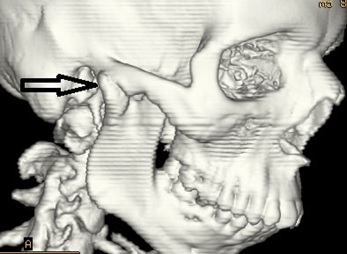

Total 10 patients with Temporomandibular Joint (TMJ) ankylosis reporting to the outpatient department of Oral and Maxillofacial Surgery, Maharaja Ganga Singh Dental College and Research Centre, Sri ganganagar, Rajasthan, India were included irrespective of age, sex, caste and socioeconomical status. Diagnosis of TMJ ankylosis was based on the basis of clinical assessment as Maximum inter-incisal Mouth Opening (MMO) [Table/Fig-1] and other cardinal signs of ankylosis [1] followed by radiographic assessment using Postero-anterior (PA) mandible view, Orthopantomogram (OPG), lateral oblique view and CT scan which showed various degrees of condylar involvement with condyles varying from normal size to a large spherical mass involving the condylar process as well as the coronoid process [Table/Fig-2].

3D CT scan showing ankylotic mass.